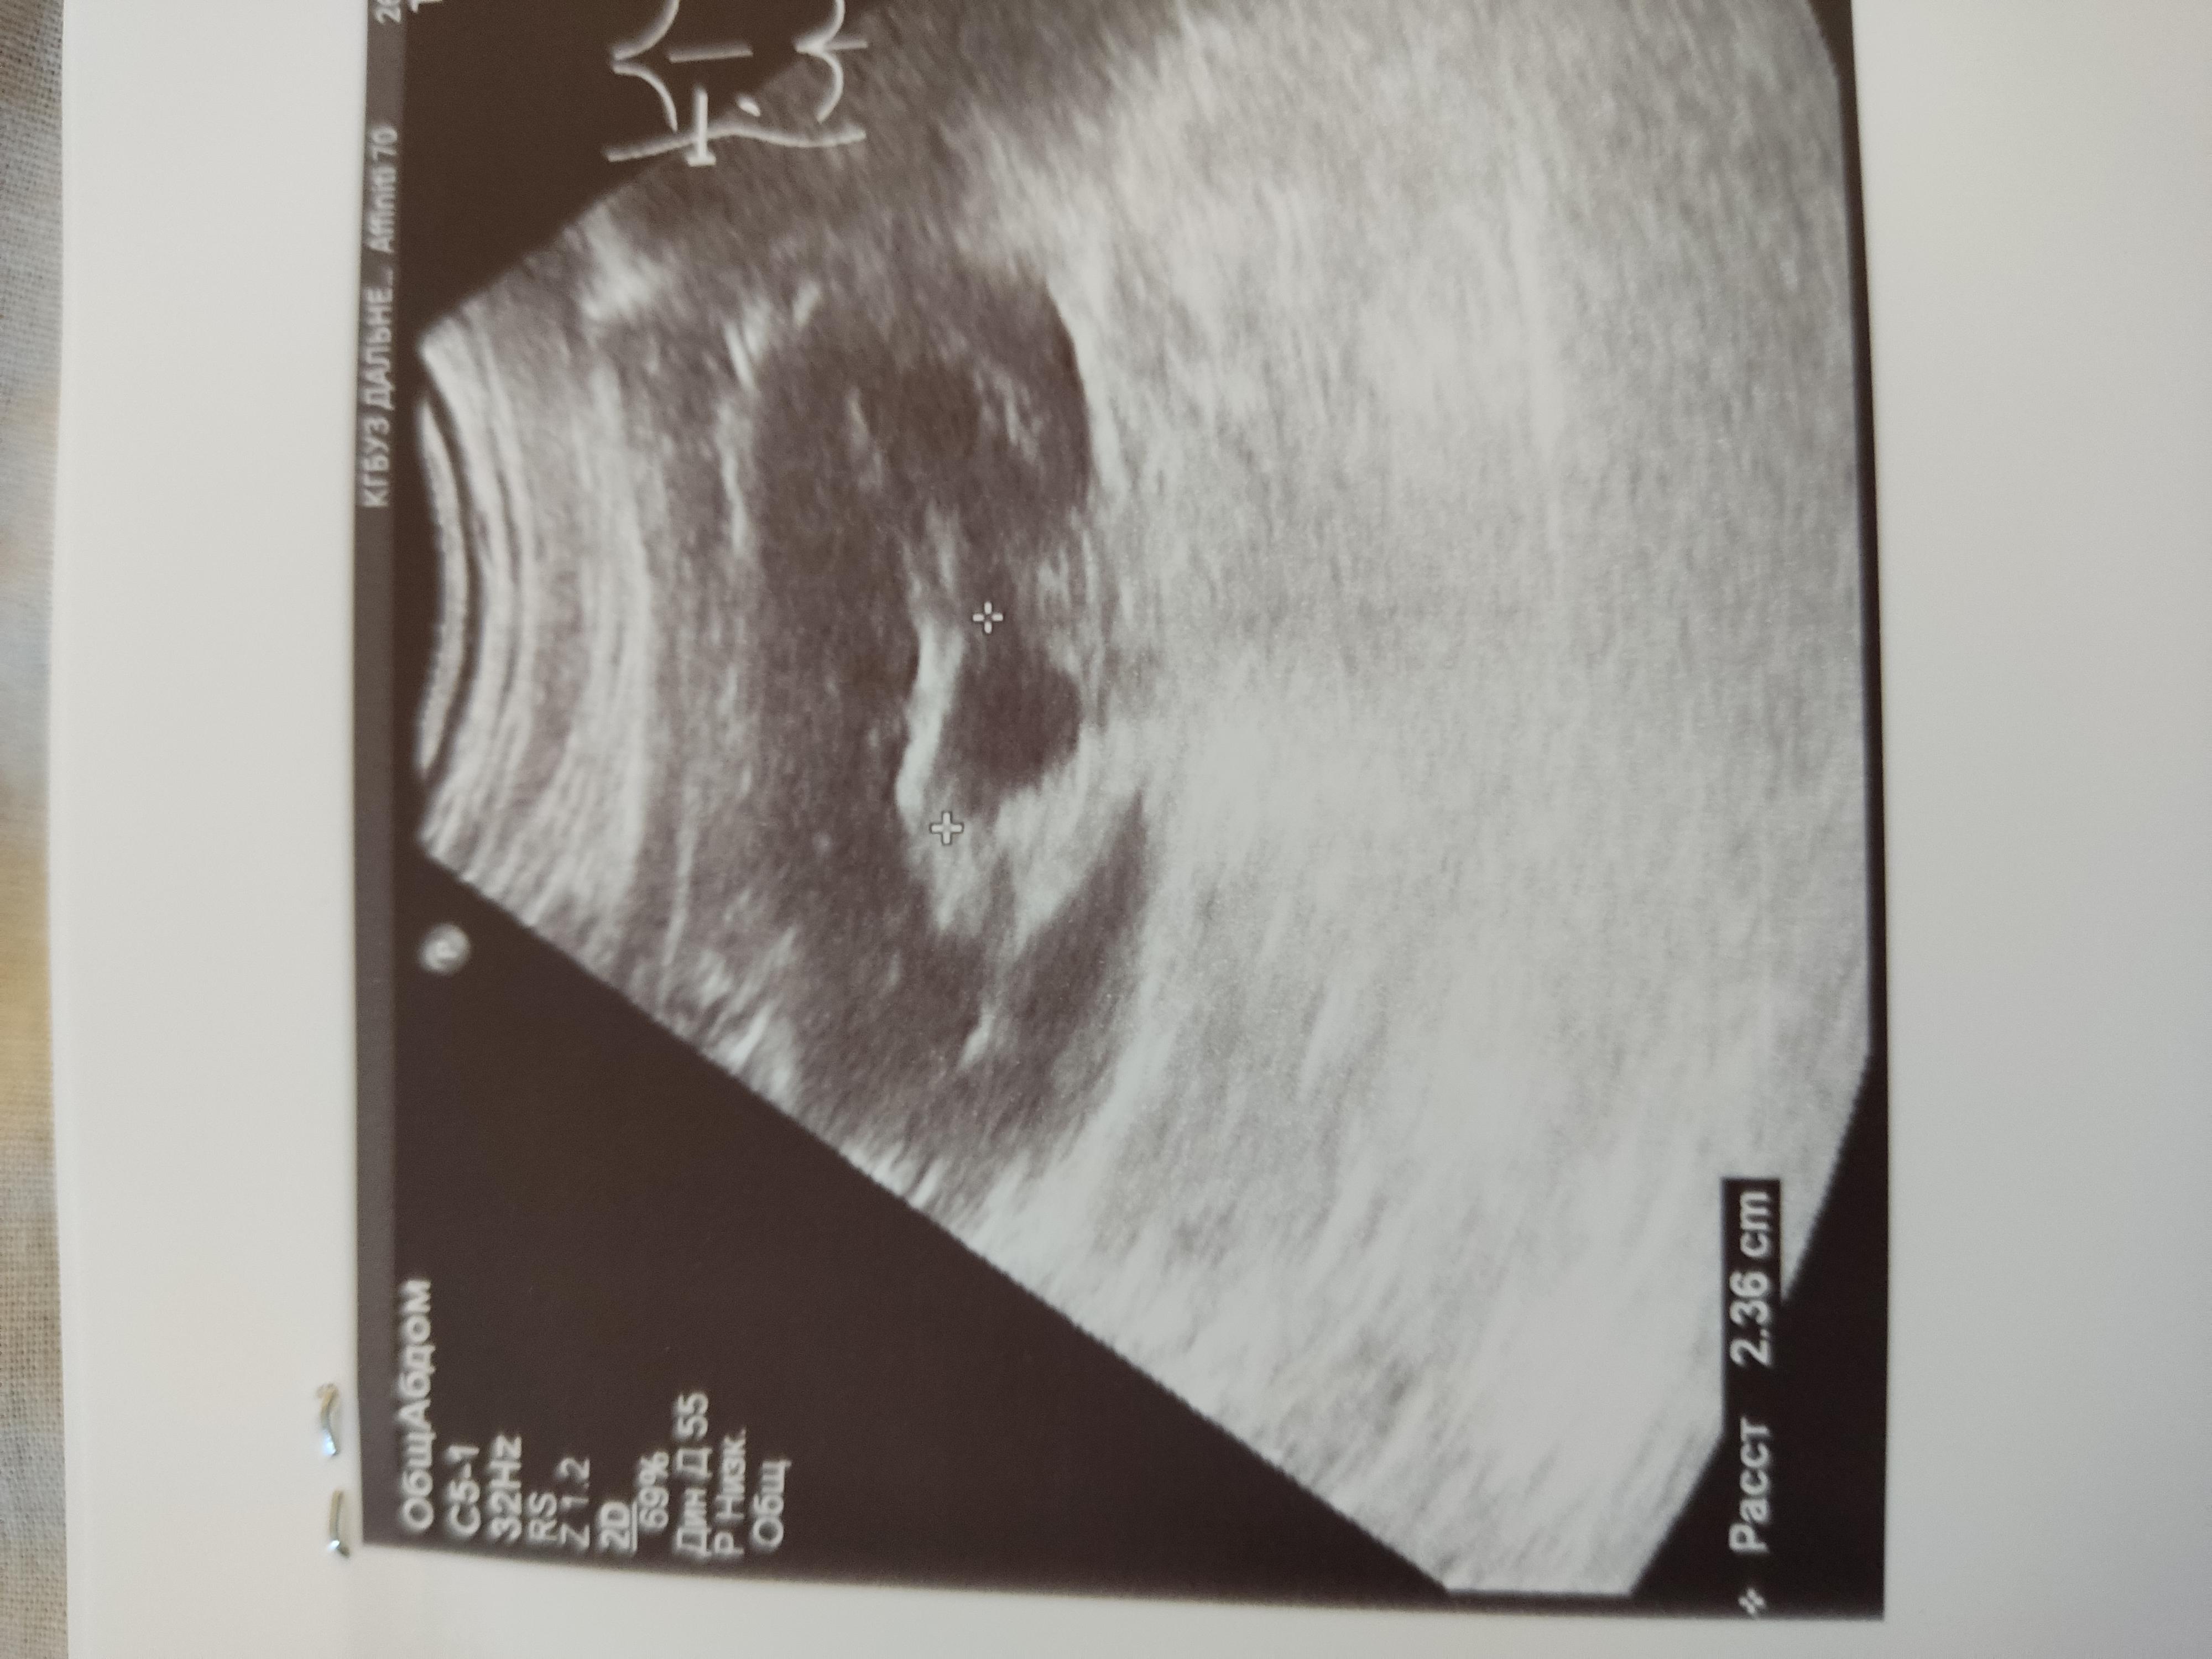

Дд. Помогите расшифровать УЗИ. Камень в почке, ужасные боли. Что можно сделать, чтоб облегчить их и ускорить выход камня? И выйдет ли каиень такого размера? Спасибо

Вам нужно начать с визита к врачу урологу на очный прием. Пройти обследование. Возможно потребуется выполнение компьютерной томографии для точной диагностики и точного выявления локализации камня и его размера. Без обследования, в первую очередь компьютерной томографии, принять решение о возможности или невозможности самостоятельного отхождения камня невозможно.